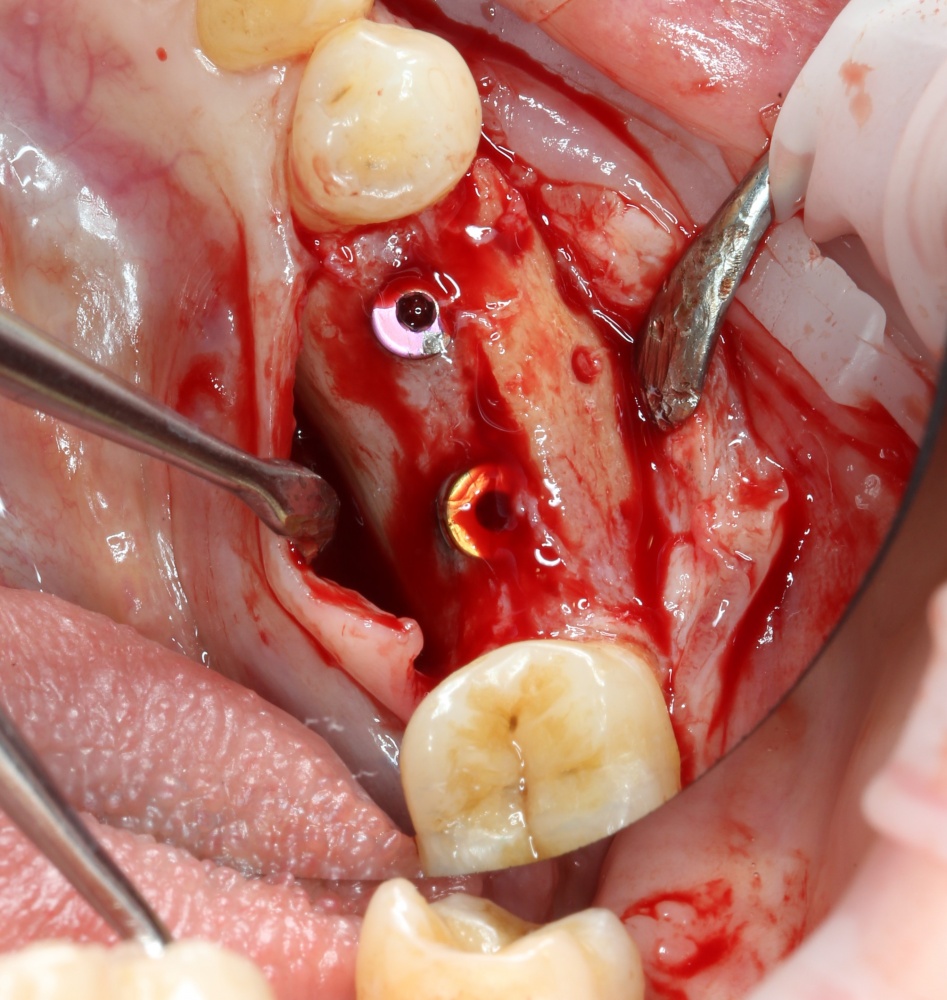

Теперь можно готовить лунки под импланты:

A09A5459 (2)

В данном случае я планирую установить импланты Nobel Replace Conical Connection:

A09A5461 (2) A09A5462 (2)

Операция почти закончена. Обратите внимание, на два момента:

1. Блок явно больше, чем нужно. Это связано с тем, что в процессе интеграции происходит атрофия графтов (причем, абсолютно любых), и мы должны закладывать этот уровень атрофии при планировании объемов костной пластики. В среднем, плюс 30% к тому, что нам нужно.

2. Между блоком и принимающим ложем есть пустое пространство. Поэтому область операции необходимо изолировать барьерной мембраной от быстро растущих мягких тканей. Я использую Geistlich BioGide 25×25 mm: